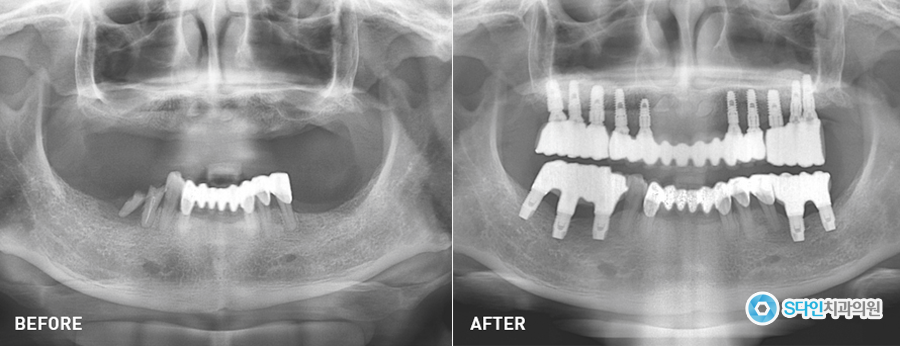

유치가 빠지고 새로 난 치아를 우리는 '영구치'라고 부르는데요. 기존에는 영구치가 빠지면 틀니로 대체하곤 했습니다. 하지만 영구치를 대체하기에는 불편한 점이 많았죠. 그래서 발명된 것이 바로 잇몸 뼈에 치아를 심는 임플란트입니다.

임플란트 시술이 대중화 되면서 임플란트에 대해서 많이 고민하고 계실텐데요. 오늘은 임플란트 시작 전, 꼼꼼하게 따져봐야 할 사항 5가지를 소개해드리겠습니다.